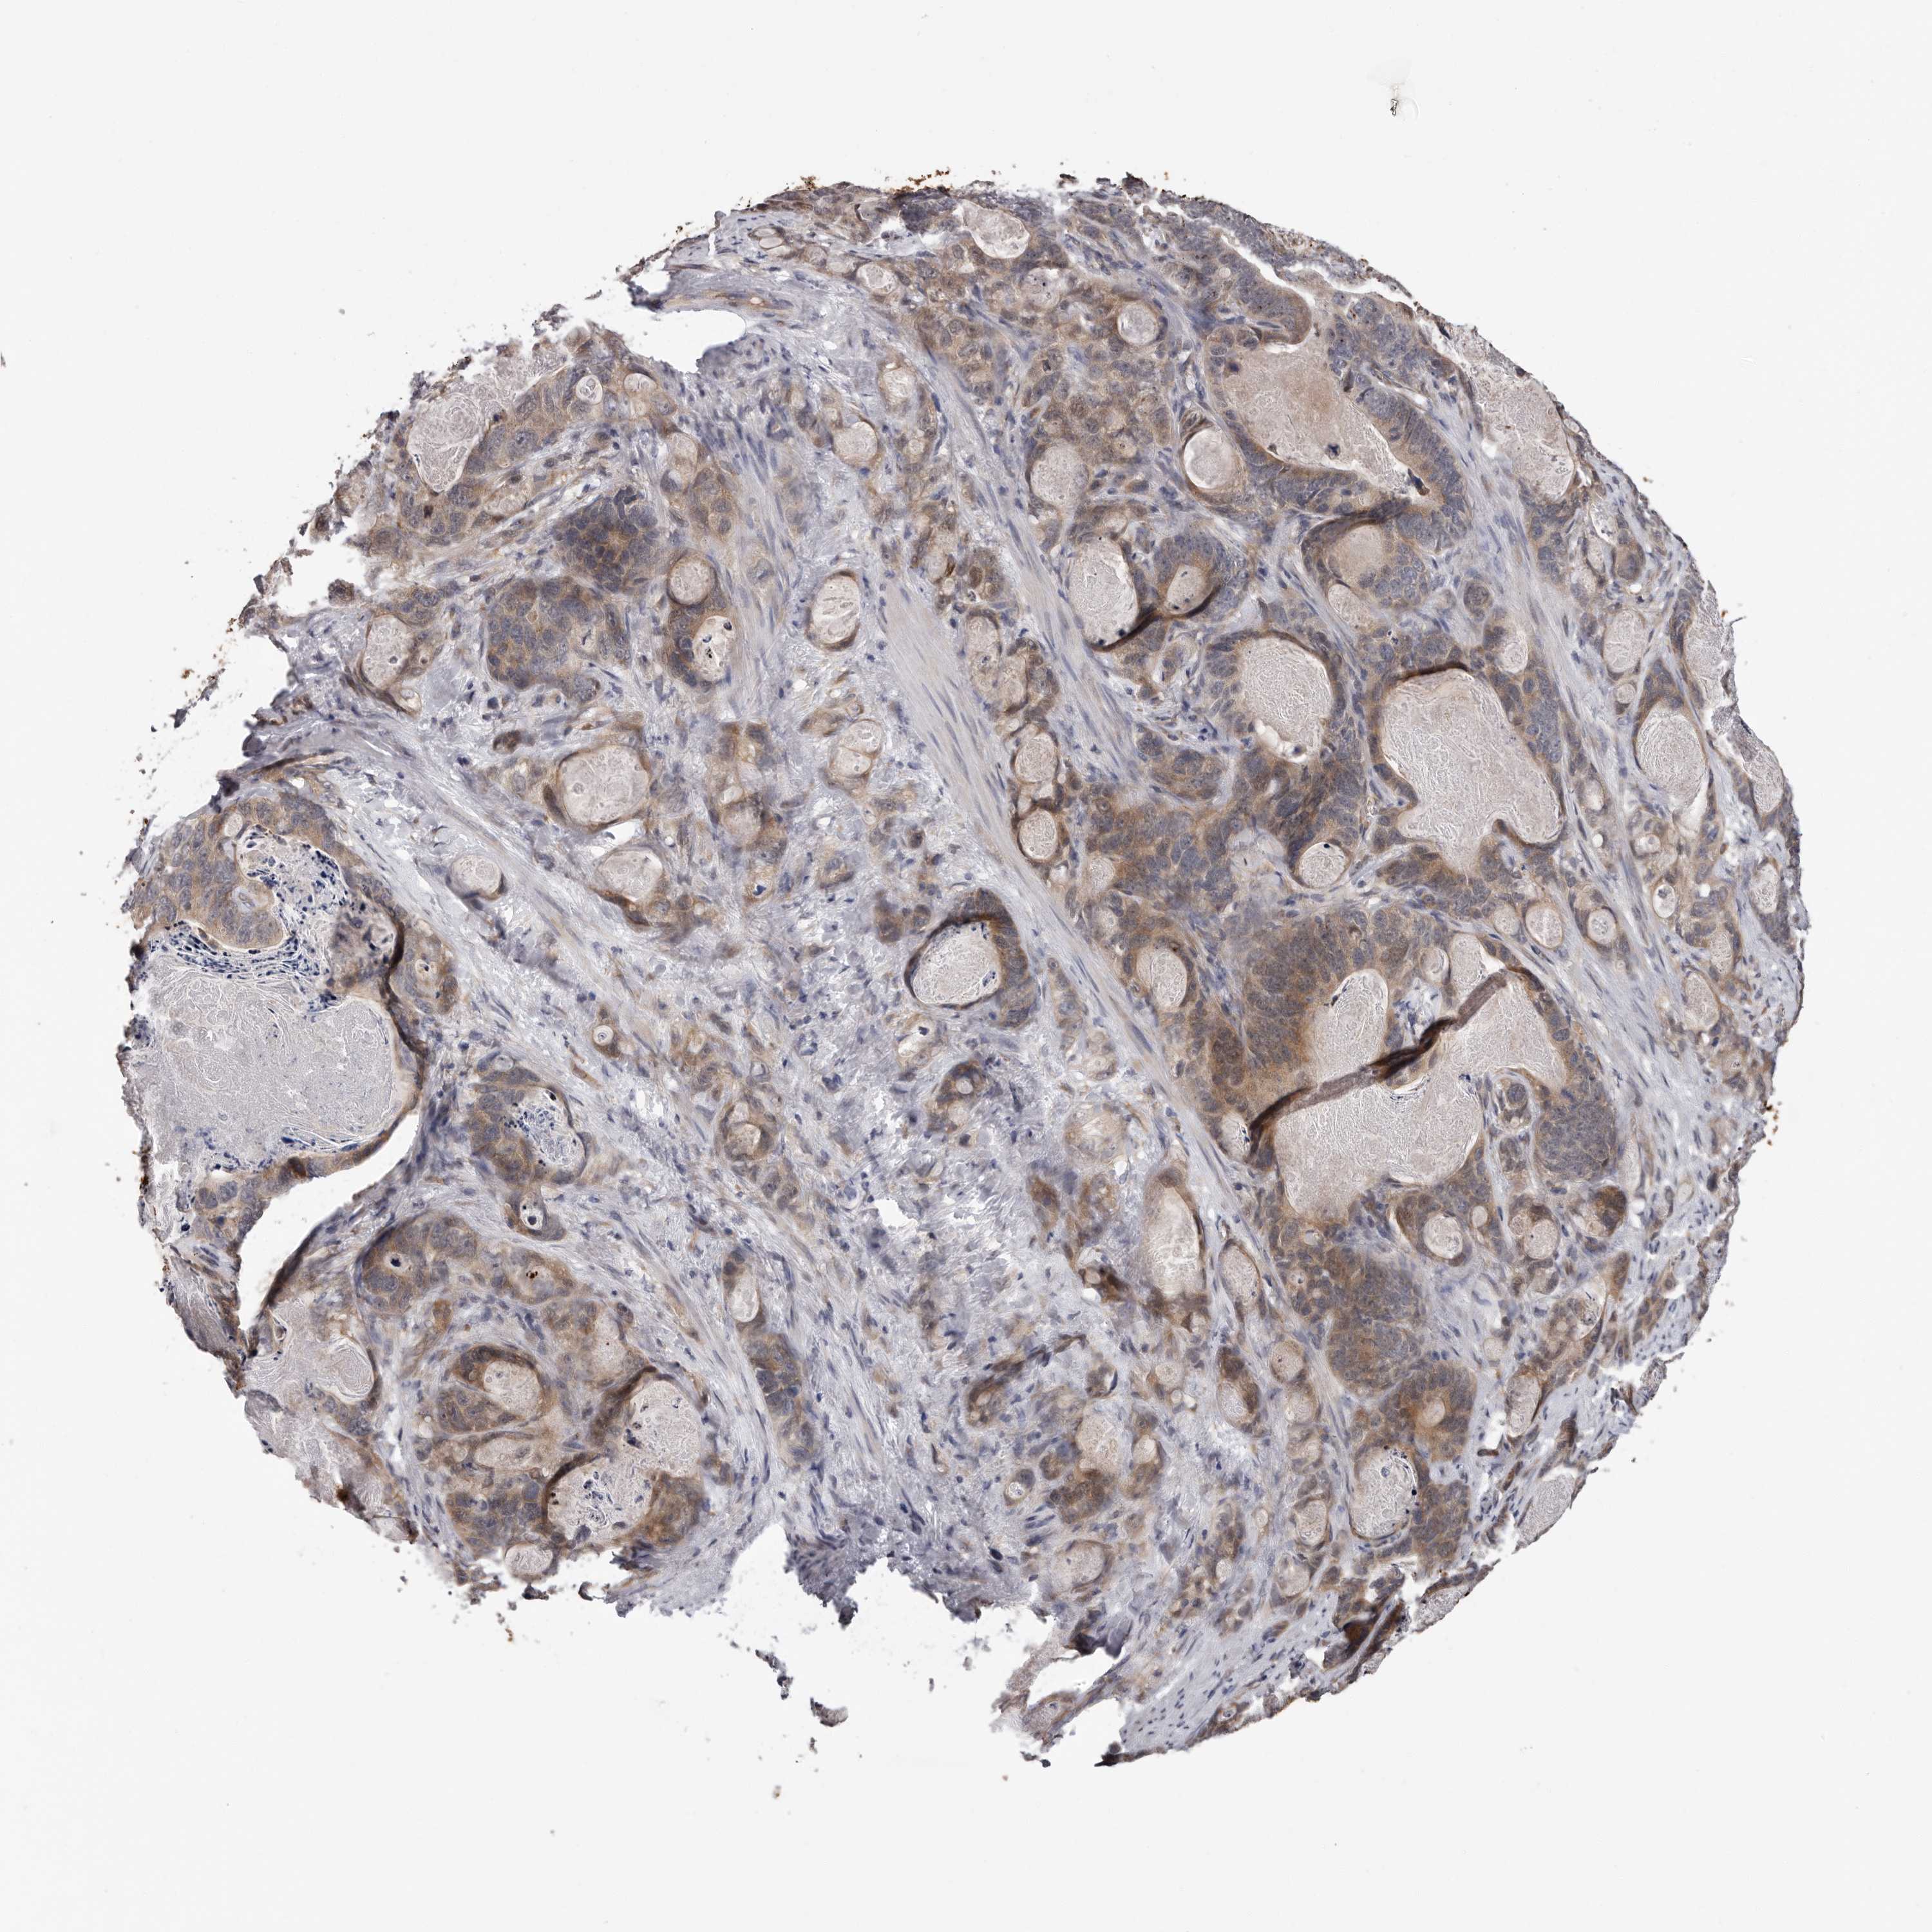

STOMACH CANCER - Protein expressioni

A mouse-over function shows sample information and annotation data. Click on an image to view it in a full screen mode. Samples can be filtered based on level of antibody staining by selecting one or several of the following categories: high, medium, low and not detected. The assay and annotation is described here.

Note that samples used for immunohistochemistry by the Human Protein Atlas do not correspond to samples in the TCGA dataset.

Antibody stainingi

Antibody staining in the annotated cell types in the current human tissue is reported as not detected, low, medium, or high, based on conventional immunohistochemistry profiling in selected tissues. This score is based on the combination of the staining intensity and fraction of stained cells.

Each image is clickable and will lead to virtual microscopy that enables deeper exploration of all samples and also displays staining intensity scores, fraction scores and subcellular localization as well as patient and tissue information for each sample.

Antibody HPA028377

Antibody HPA028438

Staining

High

Medium

Low

Not detected

Intensity

Strong

Moderate

Weak

Negative

Quantity

>75%

75%-25%

<25%

None

Location

Nuclear

Cytoplasmic/membranous

Cytoplasmic/membranous,nuclear

Adenocarcinoma, NOS